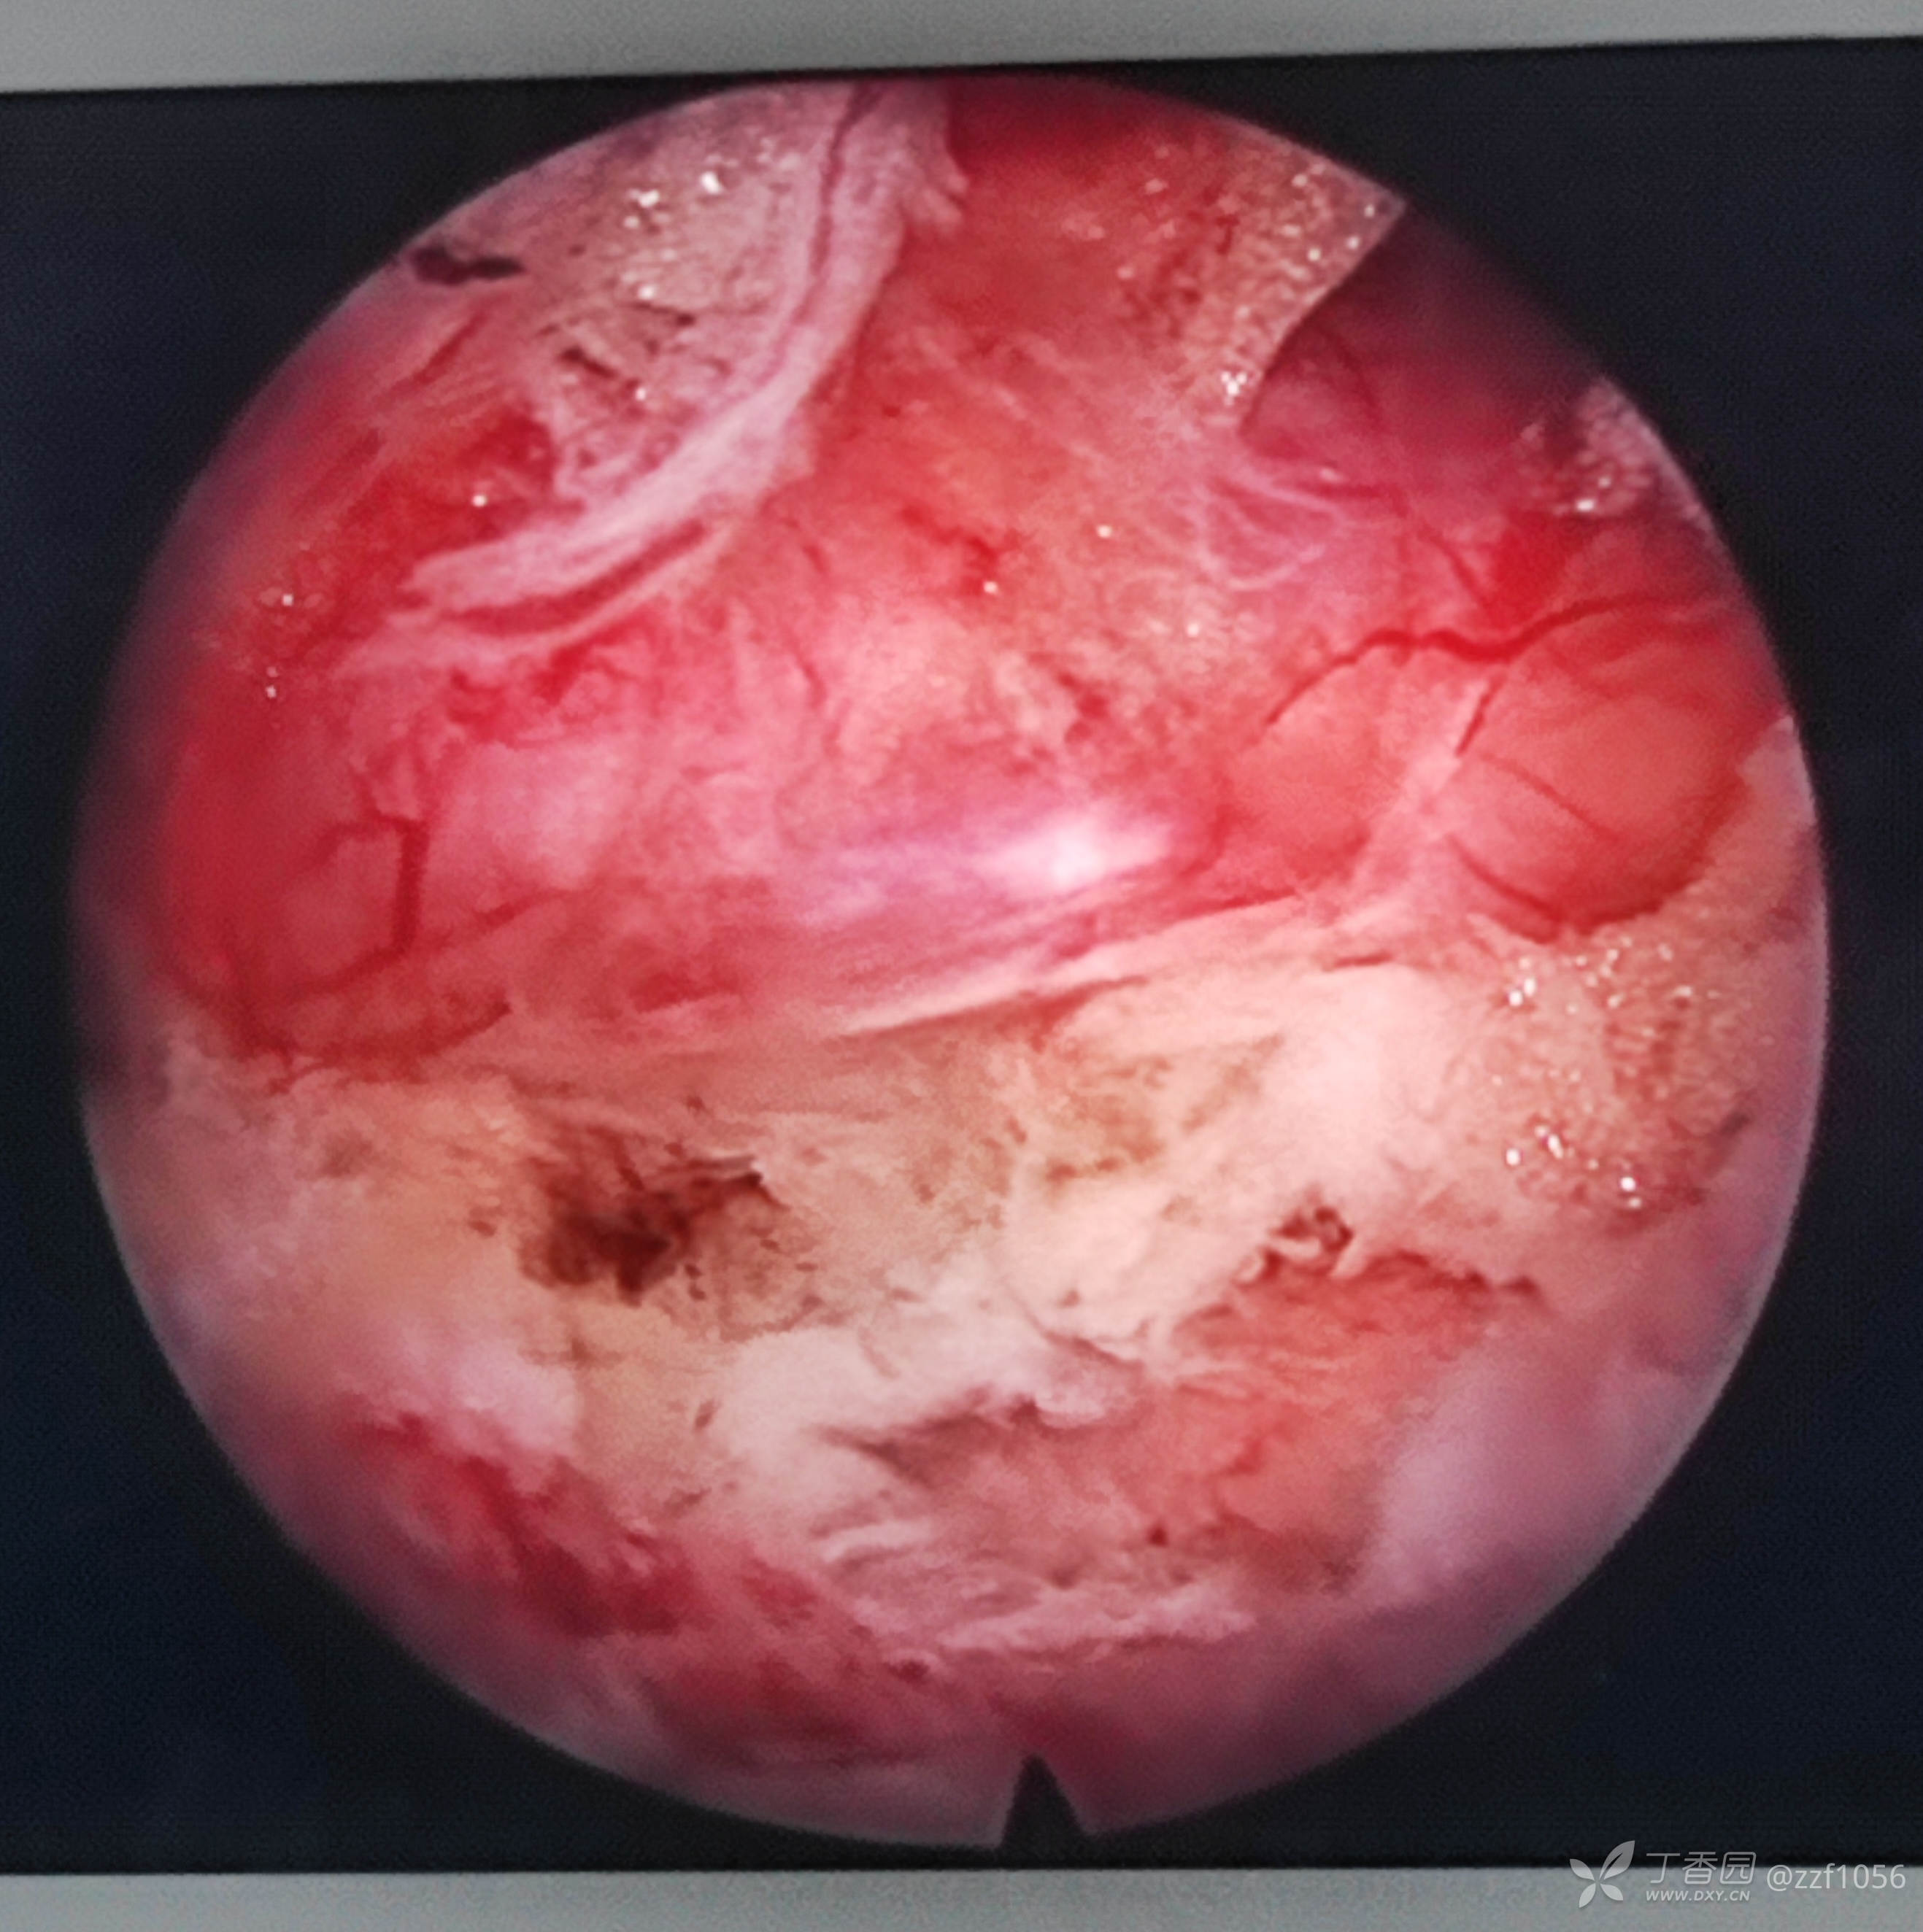

突出挤压行走根严重

减压后

很大一块